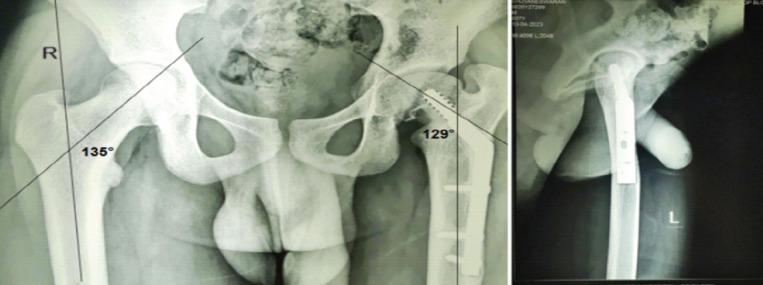

Coxa vara is a rare pediatric hip disorder characterized by a reduced femoral neck shaft angle (NSA) (<120°), resulting in limb length discrepancy, gait abnormalities, and hip dysfunction. While developmental coxa vara has characteristic radiological features, atypical presentations with unknown etiologies are infrequently reported.

A 7-year-old boy with left hip pain presented without any history of trauma or systemic illness. Radiographs and computed tomography imaging revealed coxa vara with a transcervical femoral neck fracture with a mixed predominantly sclerotic lesion in the femoral neck. A closed-wedge valgus osteotomy was performed with internal fixation using a locking plate and screws placed proximal to the physis. Intraoperative biopsy ruled out tumor or infection. Although initial outcomes were favorable, recurrence of coxa vara and femoral neck fracture occurred after 1 year and 9 months. Revision surgery involved medial open-wedge osteotomy with bone grafting and fixation using a pediatric dynamic hip screw, with the lag screw crossing the physis for stability. At the 8th-year follow-up, the patient was pain-free, with minimal limb shortening and good functional mobility. X-rays showed solid radiographic union, disappearance of the previously noted sclerotic lesion in the left femoral neck, and maintenance of the NSA.

This case involves coxa vara with atypical radiographic features, complicating its classification as developmental or acquired. Initial fixation that preserved the physis resulted in recurrence. Subsequent fixation crossing the physis, along with correction of the Hilgenreiner epiphyseal (HE) angle, effectively prevented recurrence. At 8-year follow-up, the patient demonstrated a good clinical and radiological outcome.

The HE angle is a critical prognostic factor in predicting the recurrence of coxa vara. Surgical stability should take precedence over physeal preservation.

髋内翻是一种罕见的儿童髋关节疾病,其特征为股骨颈干角(NSA)减小(<120°),导致肢体长度不等、步态异常和髋关节功能障碍。虽然发育性髋内翻具有典型的放射学特征,但病因不明的非典型表现却鲜有报道。

一名7岁男孩因左髋疼痛就诊,无任何外伤或全身疾病史。X线片和计算机断层扫描成像显示髋内翻合并经颈股骨颈骨折,股骨颈有一个以硬化为主的混合性病变。采用闭合楔形外翻截骨术,使用锁定钢板和螺钉在骨骺近端进行内固定。术中活检排除肿瘤或感染。尽管初始结果良好,但1年9个月后髋内翻和股骨颈骨折复发。翻修手术采用内侧开放楔形截骨术并植骨,并使用儿童动力髋螺钉固定,拉力螺钉穿过骨骺以确保稳定。在第8年随访时,患者无疼痛,肢体缩短最小,功能活动良好。X线片显示骨折牢固愈合,左侧股骨颈先前 noted的硬化病变消失,NSA维持正常。

本病例涉及具有非典型放射学特征的髋内翻,使其难以分类为发育性或后天性。最初保留骨骺的固定导致复发。随后穿过骨骺的固定,以及对希尔根赖纳骨骺(HE)角的矫正,有效防止了复发。在8年随访时,患者显示出良好的临床和放射学结果。

HE角是预测髋内翻复发的关键预后因素。手术稳定性应优先于骨骺保留。